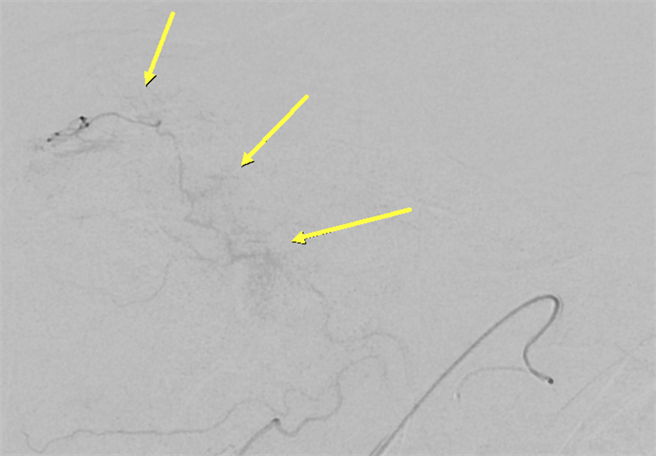

醫師先將積水抽出後,再進行微細血管栓塞術,經由X光導引下,將微小導管從手部撓動脈置入放至肩膀疼痛處,再把栓塞藥劑慢慢注入到疼痛部位血管,消除發炎造成的新生血管。李政君說,單側手術時間僅花1個小時,無須住院,術後患者疼痛感明顯降低。